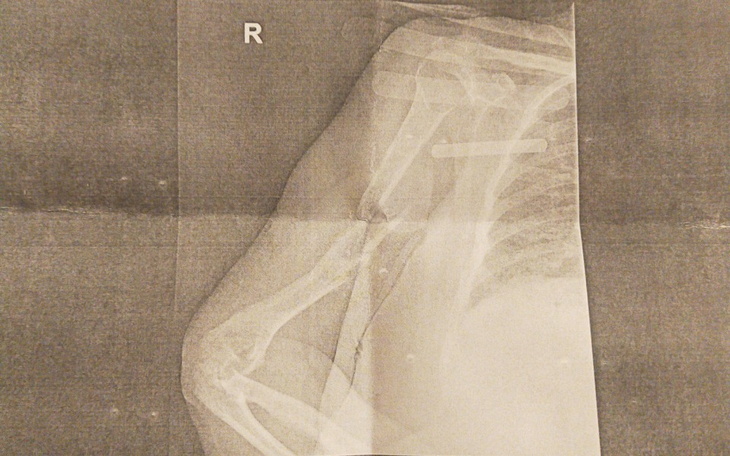

Spiralne złamanie trzonu kości ramiennej prawej z odłamem pośrednim. Złamanie od 18 czerwca 2021, brak zrostu do dziś. Ręka będzie operowana w Gdańsku na Akademii. Pilnie potrzebujemy na operację ręki mojej mamy!! Mama ma 66 lat, utrzymuje się z niewielkiej renty KRUS. Nie jest w stanie nazbierać tak olbrzymiej kwoty w tak krótkim czasie.